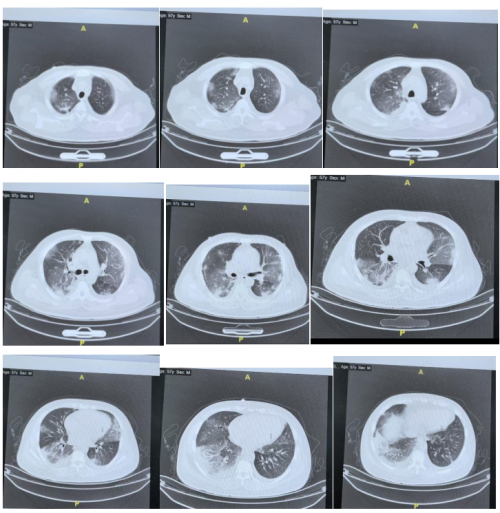

胸部CT变化:

12月8日: